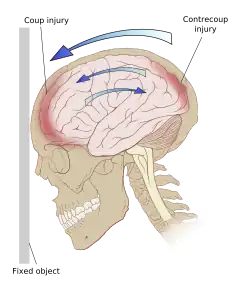

El TCE es causado por fuerzas externas a la cabeza que pueden clasificarse como fuerzas de contacto y de inercia. Las fuerzas de contacto suelen causar lesiones focales como fracturas de cráneo, contusiones y hematomas como el epidurales o subdurales. Cuando la inercia actúa sobre la cabeza causa aceleración por traslación o rotación con o sin una fuerza de contacto. Este es el caso de los «latigazos» que se producen cuando se frena bruscamente un vehículo. Dado que el cerebro no está rígidamente unido al cráneo, el movimiento de traslación por inercia del cerebro en la cavidad craneal puede causar contusiones, hematomas intracerebrales y hematomas subdurales, por impacto de la masa encefálica con las estructuras craneales. La inercia por rotación o angular suele tener un efecto más importante y puede causar daño axonal difuso. Un TCE grave puede ser resultado solamente de fuerzas de aceleración/desaceleración sin daño alguno en el cuero cabelludo.[3][15]

Existen dos tipos de daño primario: el traumatismo craneal cerrado (TCC) y el traumatismo craneal penetrante (TCP). En el TCC el impacto directo del cerebro contra el cráneo y el corte de las estructuras neurovasculares por las fuerzas de rotación o de rebote dan como resultado el daño en el cuerpo celular y los axones. Los accidentes de tráfico son colisiones a alta velocidad muy rápida y son particularmente perjudiciales debido a que las estructuras neuronales, que residen en un compartimento lleno de líquido, se mueven durante la parada repentina del cuerpo en movimiento chocando contra la bóveda craneal. Las estructuras se golpean tanto en el plano directo como en el opuesto del movimiento contra la lámina ósea interna. Esta es la base del patrón de lesión por golpe-contragolpe donde se ve una lesión contusional o en el cerebro profundo que el lugar del impacto del cráneo y 180 grados opuesto al lugar del impacto. Si hay fuerzas de rotación, las estructuras se tuercen y pueden ocurrir desgarre. Esta es la causa de la lesión axonal difusa y se ve comúnmente en TAC o MRI como hemorragias después del TCE[8]

Las contusiones se encuentran en 20% al 25% de los pacientes con TCE grave. Son lesiones heterogéneas compuestas de zonas de hemorragia puntiforme, edema y necrosis que aparecen en las imágenes de TC como áreas de hiperdensidad puntiforme (hemorragias), con hipodensidad circundante (edema), suelen estar localizadas en la cara inferior del lóbulo frontal y la cara anterior del lóbulo temporal por su relación con el ala mayor del esfenoides. También se pueden encontrar en la superficie de impacto y en la superficie contraria a este, el llamado efecto golpe-contragolpe. Cuando estas evolucionan se parecen más a los hematomas intracerebrales y su ubicación depende el posible efecto de masa.